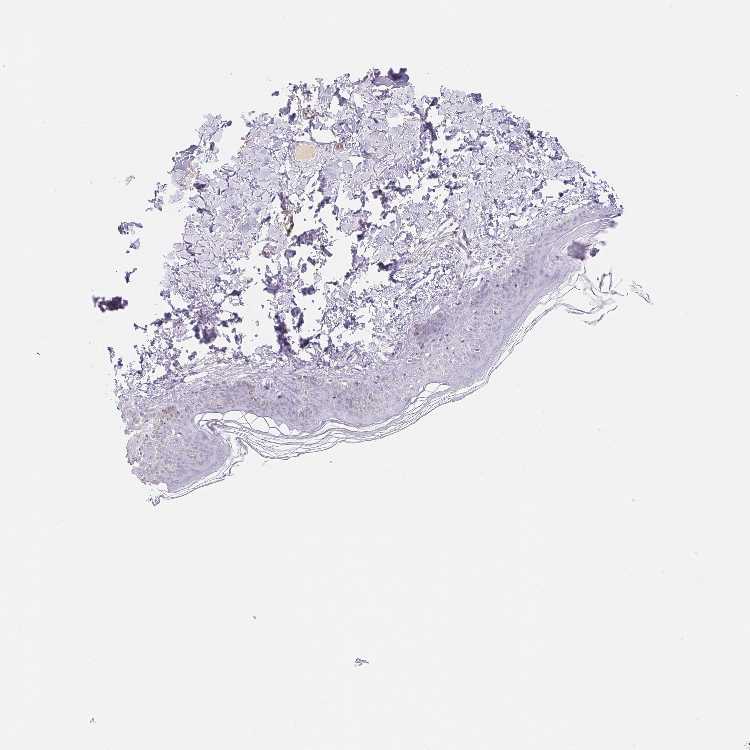

SKIN 1 - Antibody stainingi

Antibody staining in the annotated cell types in the current human tissue is reported as not detected, low, medium, or high, based on conventional immunohistochemistry profiling in selected tissues. This score is based on the combination of the staining intensity and fraction of stained cells.

Each image is clickable and will lead to virtual microscopy that enables deeper exploration of all samples and also displays staining intensity scores, fraction scores and subcellular localization as well as patient and tissue information for each sample.

Antibody HPA059150

Langerhans Not detected

Fibroblasts Not detected

Keratinocytes Not detected

Melanocytes Not detected